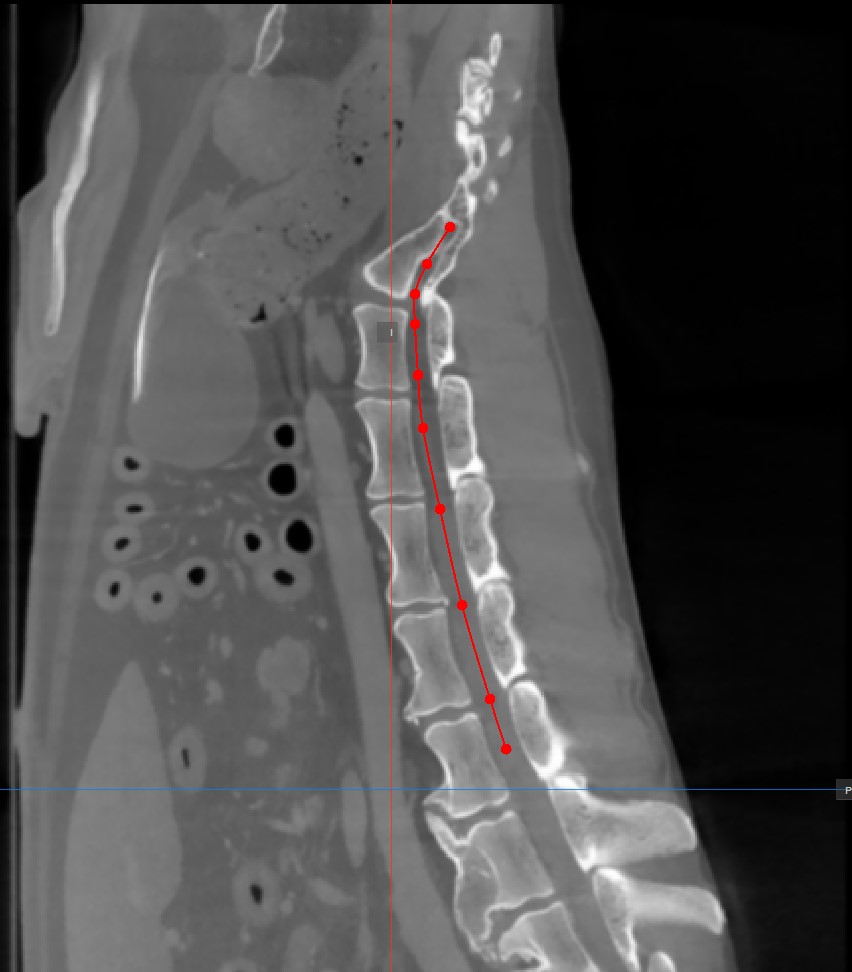

Add Curved Path Points

The Curved MPR requires a user-drawn path in order to generate the cross-sectional images. Select the Add CMPR Point tool located at the bottom section of the CMPR view to draw the required path.

• The points generating the path have to be placed on one of the three available standard MPR viewports on the right side of the window. Choose the most appropriate plane for the requirements.

• At least two points have to be placed on the images in order to generate the path. The CMPR view will be more detailed when more points are used to draw the path.

• To complete the path, toggle the Add CMPR Point tool again, or double-click with the mouse on the image after placing the last point of the path. The path will be marked in green once it’s finalized.